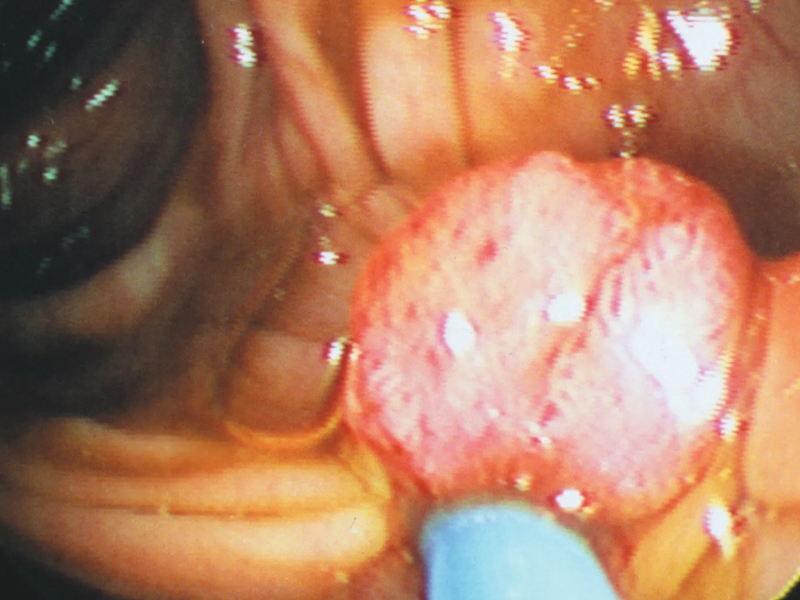

一般人很難把黑斑與胃腸息肉這兩種不相干的東西聯想在一起,但這種「黑斑息肉症候群」的典型表現就是嘴唇周圍、口腔內、鼻子、手指或腳趾側邊出現黑斑,而一旦進行大腸鏡檢查,往往會發現腸壁生了許多息肉,最多甚至可以多達上百顆。

黑斑息肉症候群是一種以消化道錯鉤瘤性息肉和皮膚黏膜、肢端色素沉著為主要特徵的染色體顯性遺傳性疾病,發生率大約在 2 萬 5000 到 30 萬分之 1 ,前面所說會出現黑斑的部位,手指、腳趾有可能隨著年齡增長而淡化,但嘴唇週邊、口腔內黏膜與鼻子上的黑斑卻會持續存在。

一般在嘴唇或鼻子等部位出黑斑的患者往往會向皮膚科求診,希望藉由手術去除黑斑,但如果這些部位的黑斑外觀突然出現變化,就應該儘快就醫,並進行精密的檢查,而透過內視鏡的檢查去除胃腸道的小息肉,防止息肉增大或癌變。